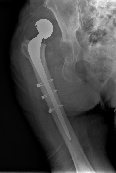

Mismatching of Different-Offset Exeter Long Stems: A Problem with Cement-In-Cement Technique: Technical Note

Francisco Ferrero-Manzanal1*, Antonio Murcia-Asensio2, Miguel Angel Suárez-Suárez3, Raquel Lax-Pérez4, Oliver Marín-Peña4